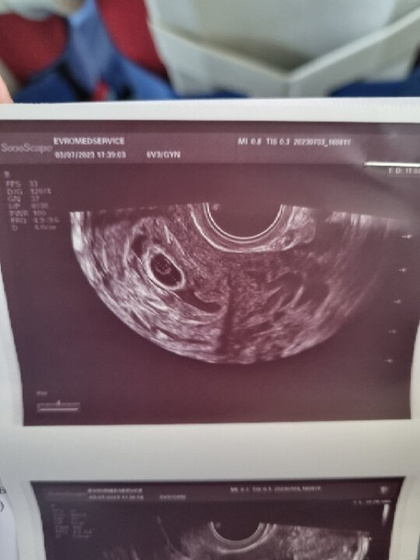

На фото видно пузырëк внутри плодного яйца. Это желточный мешок. От него малыш питается. Как мне говорила моя узистка, если желточный есть, то и эмбрион есть, просто ещё очень маленький, не разглядеть. Через неделю будет видно его и сердечко.

По УЗИ вроде видно желточный мешок, могу и ошибаться.

Через дней 5 можно уже, чтоб ЧСС сразу увидеть. Я сходила сегодня к другому узисту) тонуса нет ? Слава богу. Вот такие специалисты